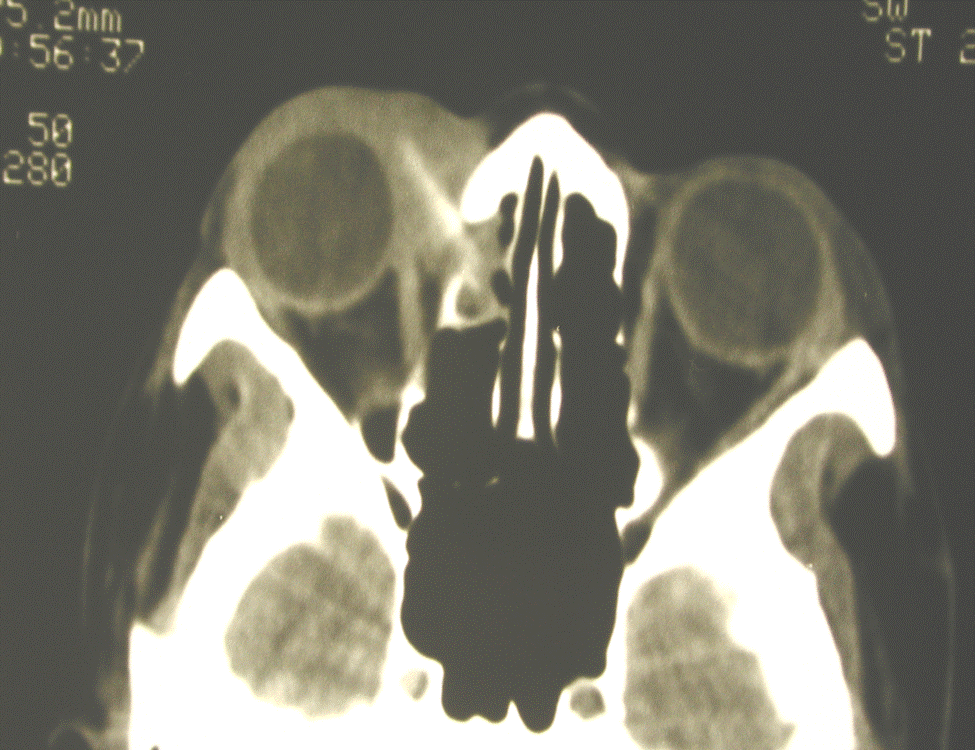

- Figure 7. CT scan of orbits showing orbital FB